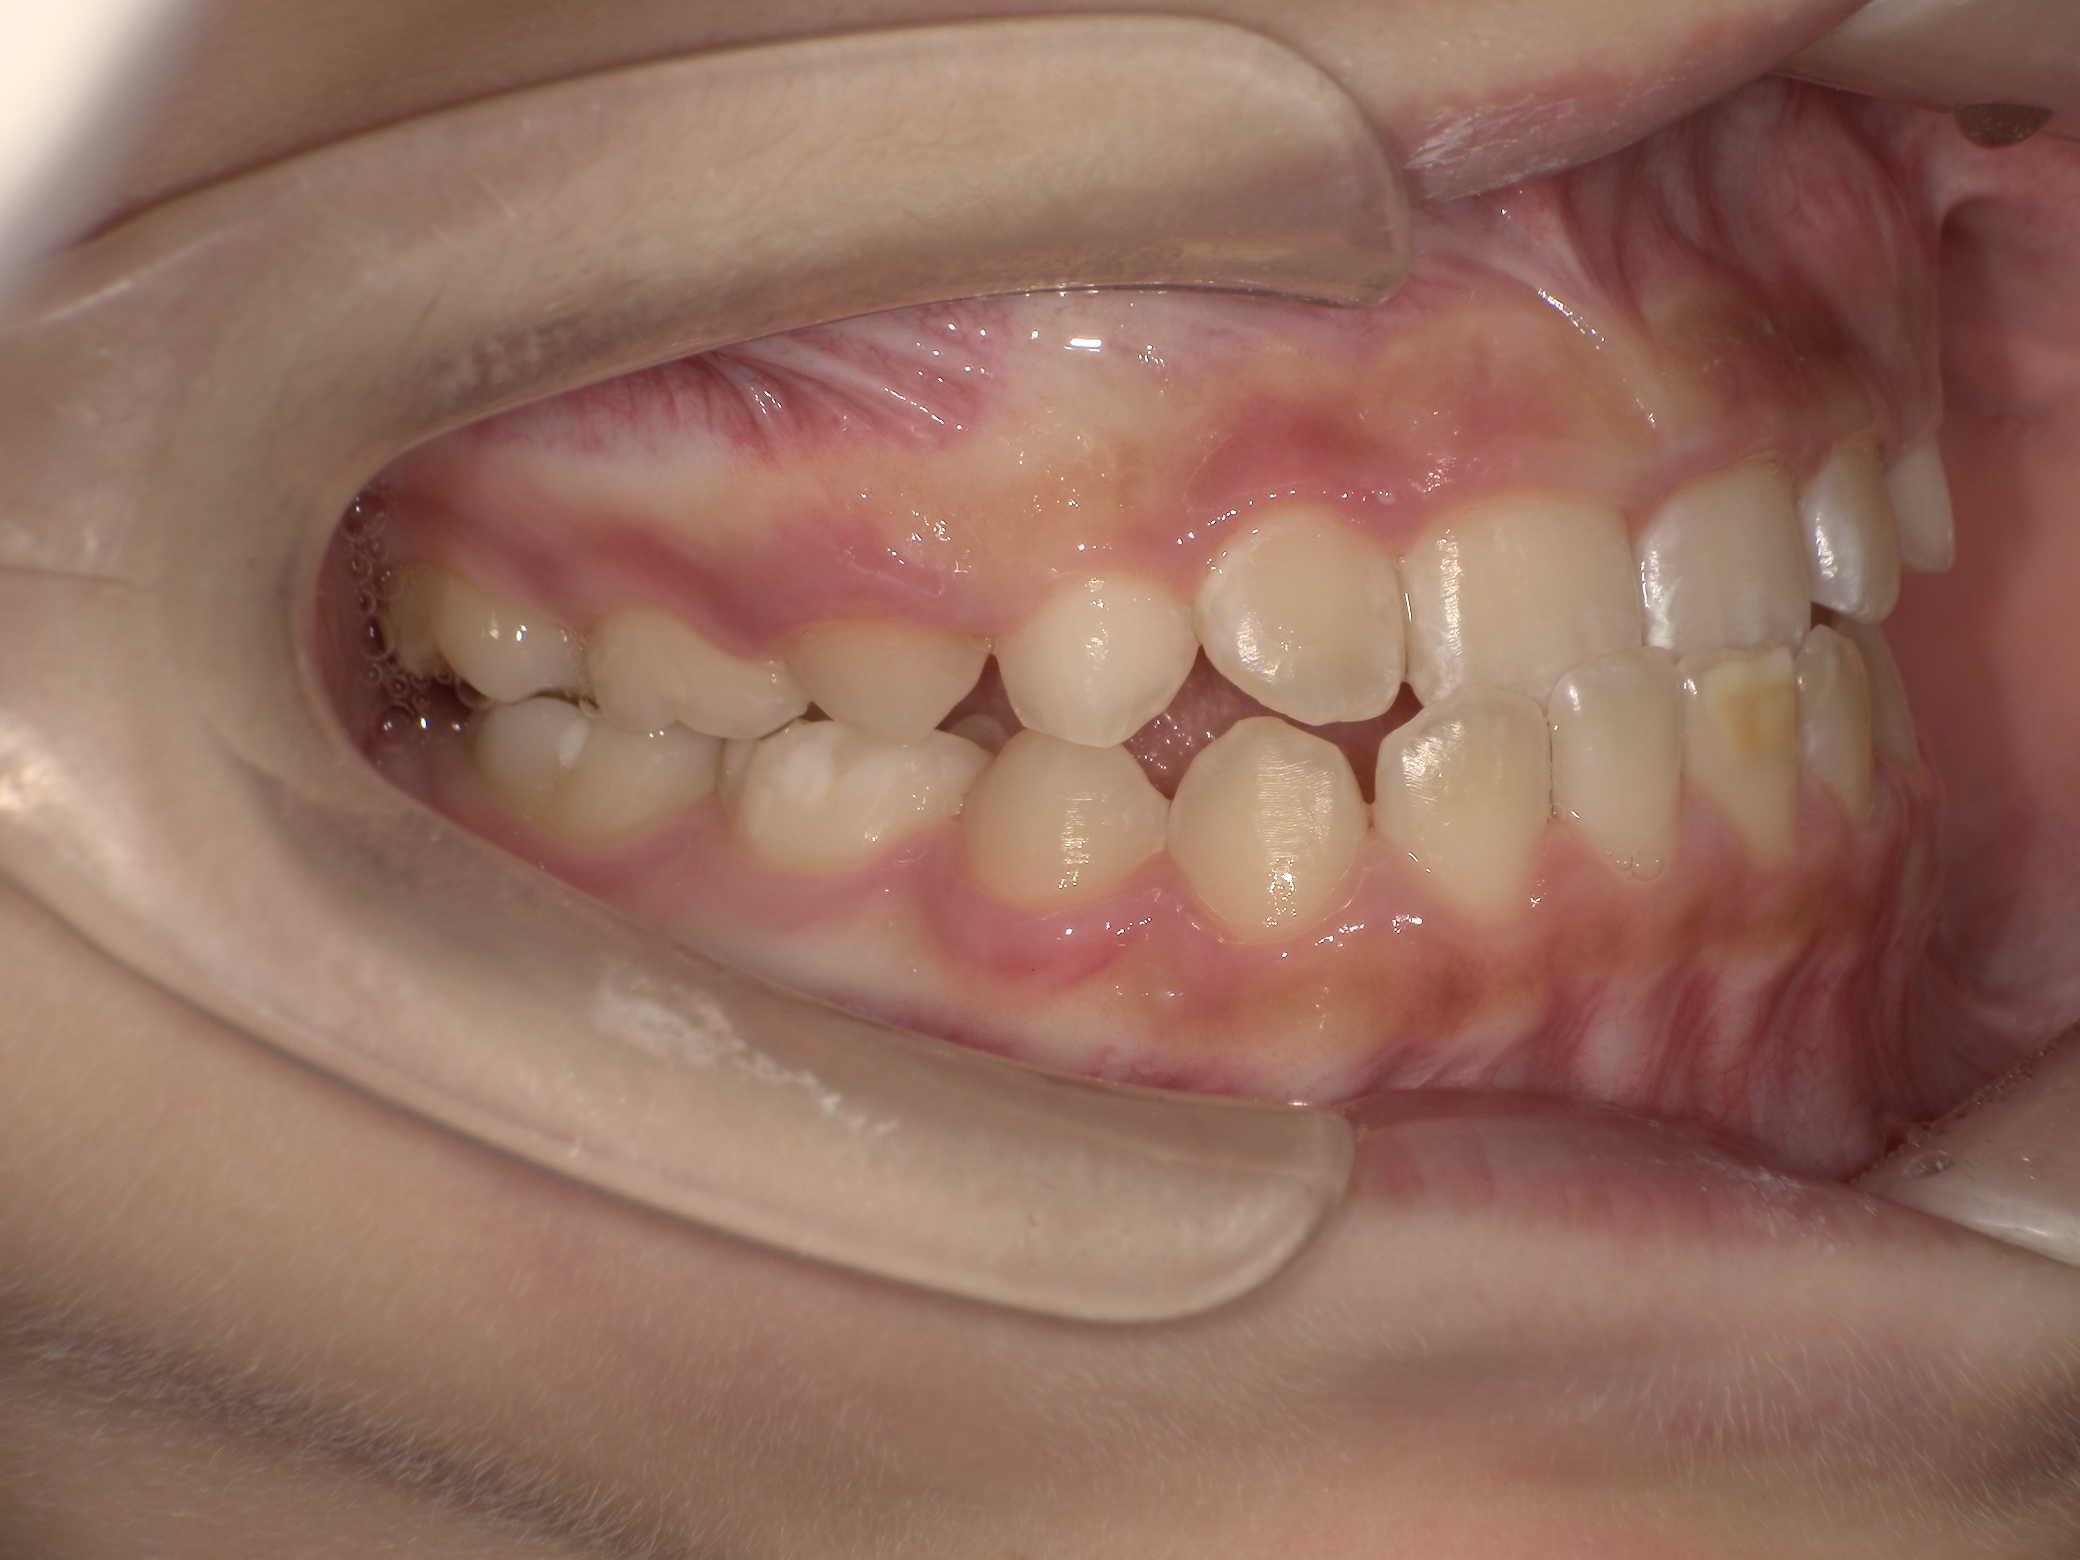

After

治療終了時(10歳1か月)